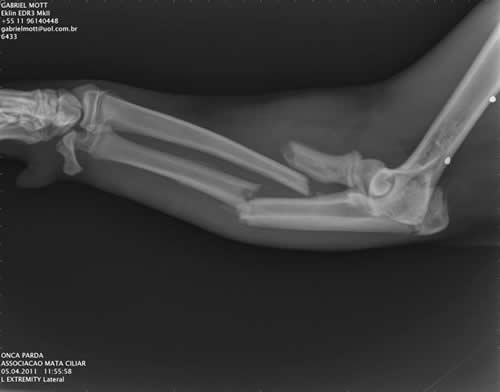

Com fraturas no braço esquerdo e na perna direita a onça também possuía fragmentos de chumbo (correspondente a arma de fogo) na região do quadril. O animal deve ter no máximo dois anos, pois ainda apresentava as linhas do crescimento nas extremidades dos ossos abertas, sinais que desaparecem apenas na idade adulta.

O Dr. José Roberto July religou o músculo que garante o movimento da perna esquerda do animal. Ele também fechou os cortes e instalou uma placa com sete parafusos e pino no braço esquerdo da onça.